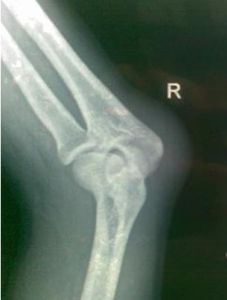

肘關節圖1.關節面 骨與骨相關節的骨面。

肘關節是由三個關節共同包裹在一個關節囊內組成的復關節。一.肱尺關節

由肱骨滑車與尺骨半月切跡構成,屬於蝸狀關節,是肘關節的主體部分。 二.肱橈關節

由肱骨小頭與橈骨小頭凹構成,屬球窩關節。

三.橈尺近側關節

由橈骨頭環狀關節面與尺骨的橈骨切跡構成,屬車軸關節。 四.關節囊

關節囊附著於各關節面附近的骨面上,肱骨內、外上髁均位於囊外。關節囊前後鬆弛薄弱,兩側緊張增厚形成側副韌帶。尺側副韌帶呈三角形,起自肱骨內上髁,呈放射狀止於尺骨半月切跡的邊緣,有防止肘關節側屈的作用。橈側副韌帶也呈三角形,附於肱骨外上髁與橈骨環狀韌帶之間。此外,在橈骨頭周圍有橈骨環狀韌帶,附著於尺骨的橈骨切跡的前後緣,此韌帶同切跡一起形成一個漏斗形的骨纖維環,包繞橈骨頭,可以防止橈骨小頭脫出。4歲以下的幼兒,橈骨頭髮育不全,且環狀韌帶較鬆弛,故當肘關節伸直位牽拉 前臂時,易發生 橈骨頭半脫位。肘關節韌帶

當肘關節伸直時,肱骨內、外上髁與尺骨鷹咀尖恰位於一條直線上,屈肘時則形成以鷹咀尖為頂角的等腰三角形,臨床上常以此鑑別 肘關節脫位或 肱骨髁上骨折。肘關節在伸直的情況下,若受暴力如跌倒時一側手掌著地,使肱骨下端向前移位、尺骨鷹咀則向後移,形成肘關節後脫位。當肘關節伸直,前臂處於鏇後位時,臂與前臂並不在一條直線上,前臂的遠側端偏向外側,二者之間形成一向外開放的鈍角,稱為提攜角。肘關節的運動